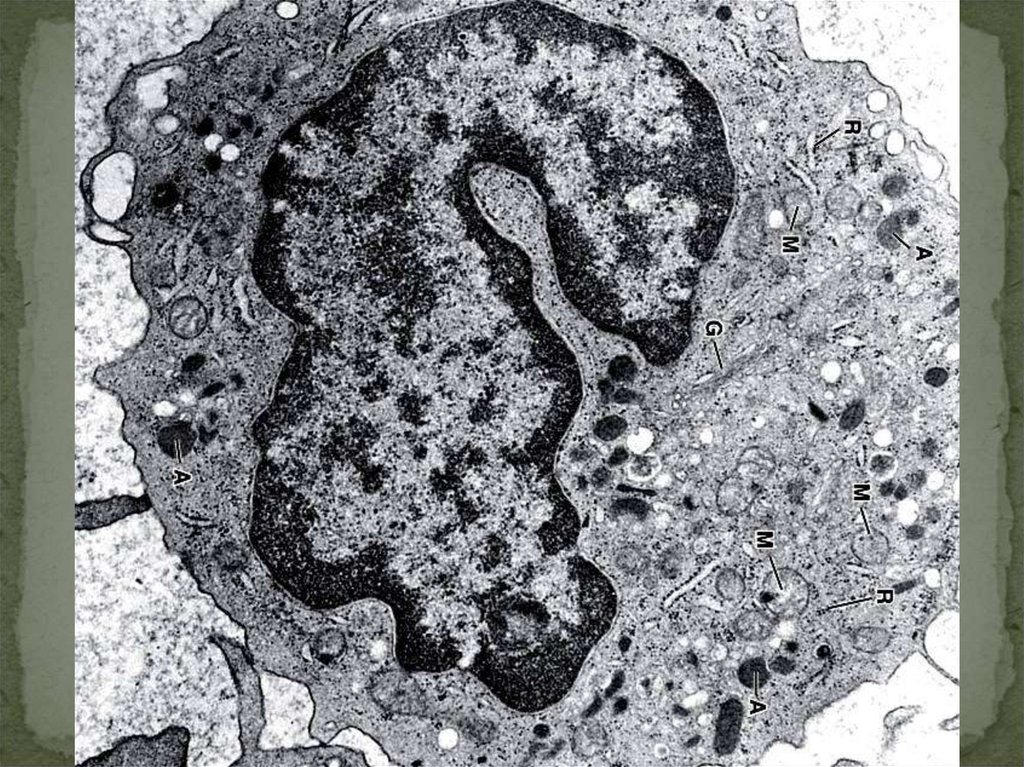

24. ЭОЗИНОФИЛЬНЫЙ ГРАНУЛОЦИТ

лизосомы

пероксидазы, MBP,

эозинофильный

нейротоксин,

гистоминаза

25.

26. ОСНОВНЫЕ ФУНКЦИИ ЭОЗИНОФИЛЬНЫХ ГРАНУЛОЦИТОВ

ПРОТИВОПРОТОЗОЙНАЯ

(АНТИГЕЛЬМИНТОЗНАЯ)

УМЕНЬШЕНИЕ ВОСПАЛЕНИЯ

АЛЛЕРГИЧЕСКОГО ХАРАКТЕРА

ФАГОЦИТОЗ БАКТЕРИЙ, НО В МЕНЬШЕЙ

СТЕПЕНИ

ПЕРЕВАРИВАНИЕ КОМПЛЕКСОВ АНТИГЕНАНТИТЕЛО (ИММУННЫЕ РЕАКЦИИ)